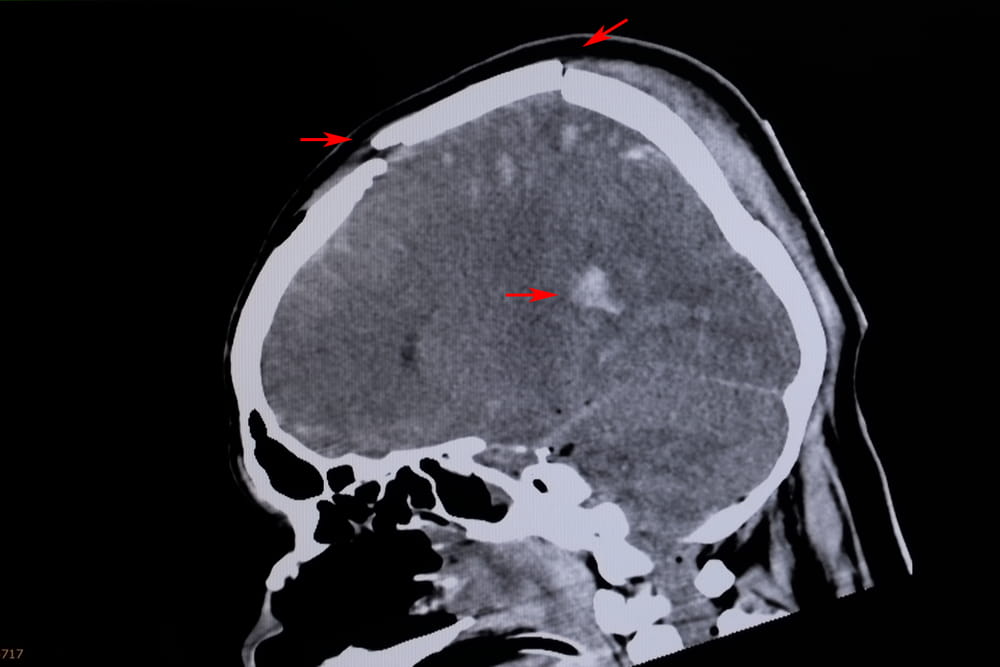

The costs of treating a traumatic brain injury can be substantial and often extend far beyond the initial emergency care. Immediate expenses may include ambulance transportation, emergency room treatment, diagnostic imaging such as CT scans or MRIs, hospitalization, and, in severe cases, surgery or intensive care. These early medical costs alone can be overwhelming.

Symptoms may appear immediately or develop over time, making TBI diagnosis and treatment complex. Medical evaluation, imaging studies, and ongoing care are often necessary to manage a traumatic brain injury. Because TBIs can have lasting effects on a person’s ability to work, maintain relationships, and live independently, they are often central issues in personal injury and medical malpractice cases.